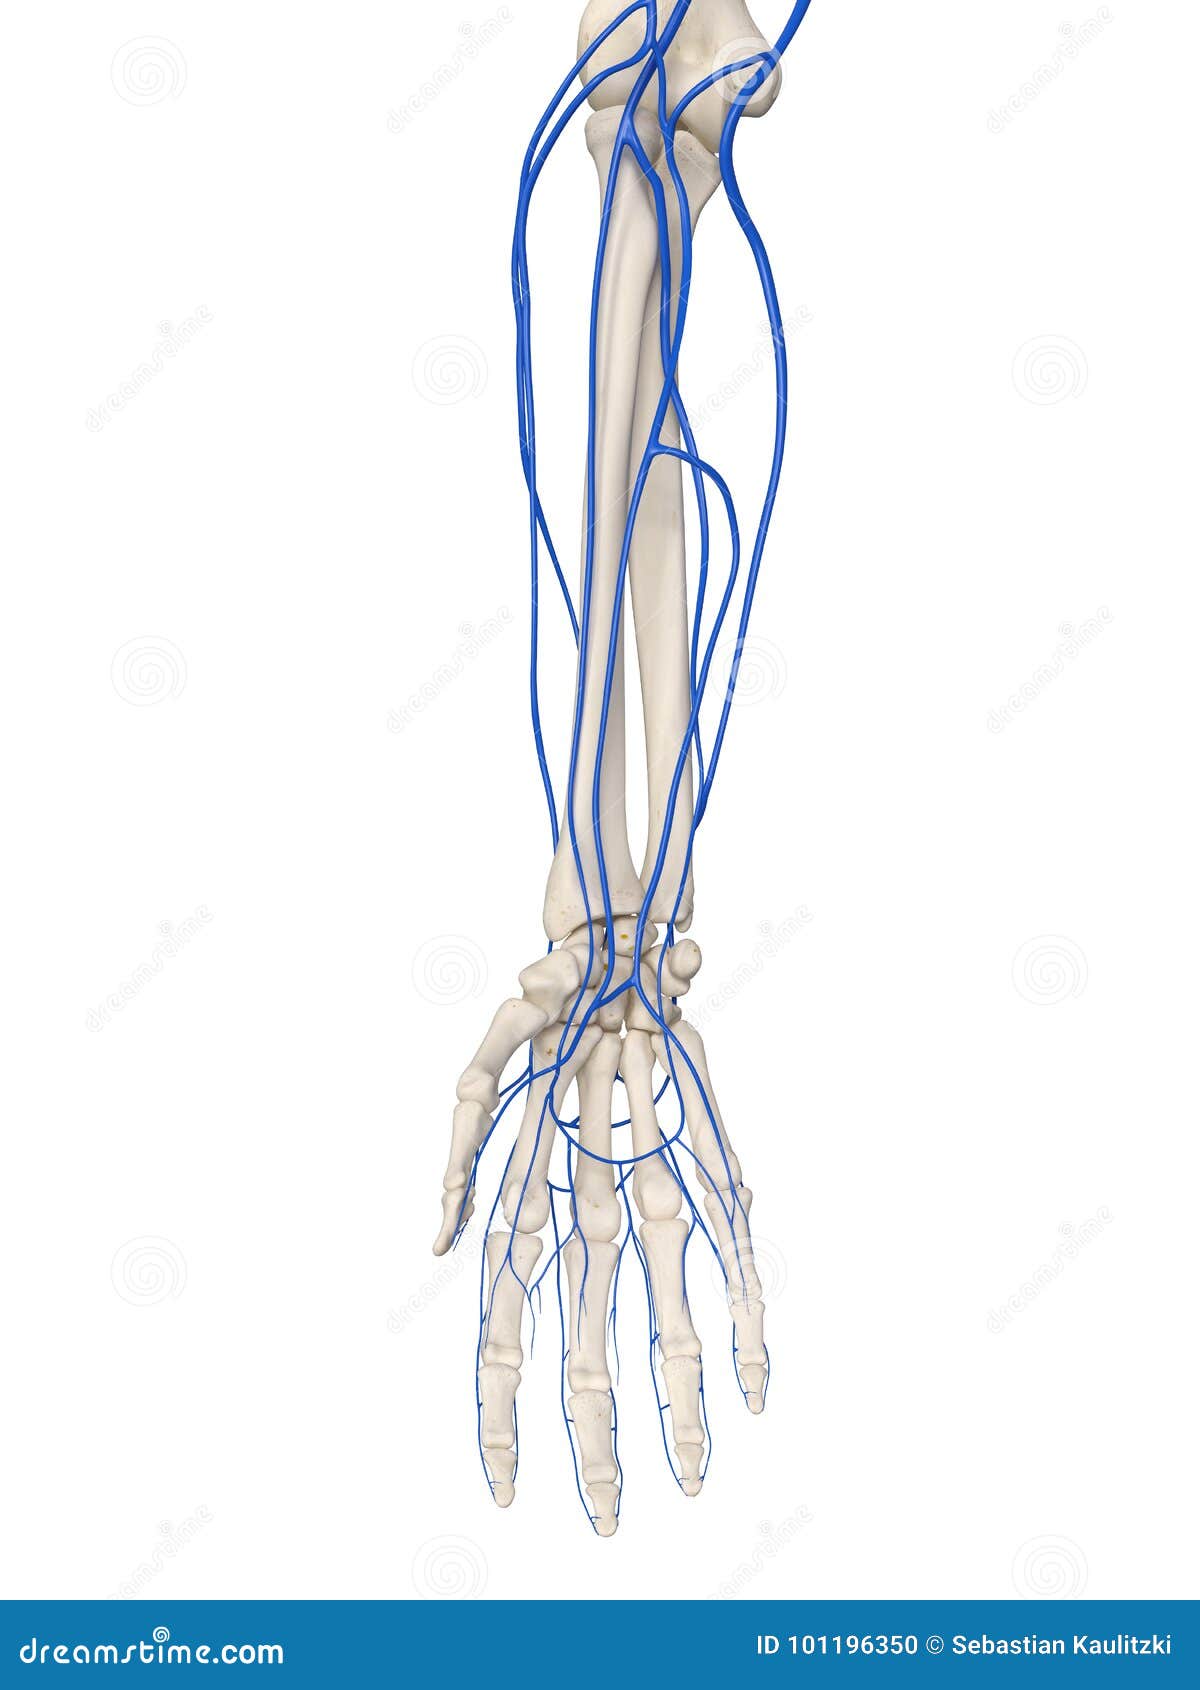

The Arm Veins Stock Illustration. Illustration Of Accurate - 101196350

www.dreamstime.com

www.dreamstime.com

veins arm illustration preview